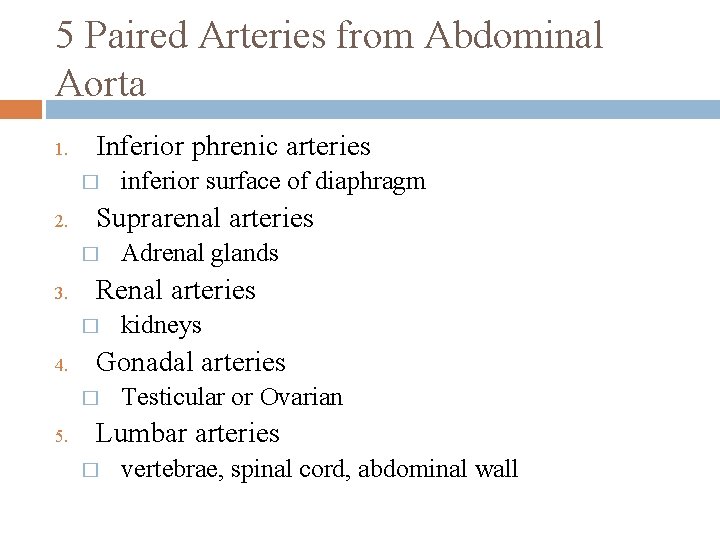

5 Paired Arteries from Abdominal Aorta 1. Inferior phrenic arteries � 2. Suprarenal arteries � 3. kidneys Gonadal arteries � 5. Adrenal glands Renal arteries � 4. inferior surface of diaphragm Testicular or Ovarian Lumbar arteries � vertebrae, spinal cord, abdominal wall